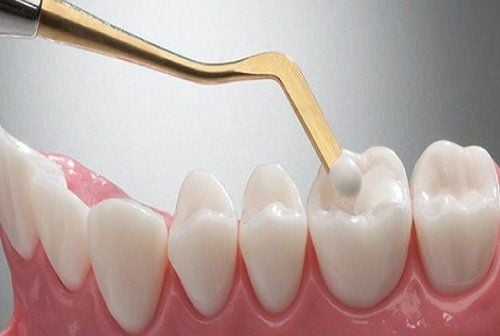

Khi nào cần trám răng thẩm mỹ?

Bạn nên đến Nha Khoa Huy Hoàng để được trám răng trong các trường hợp sau:

– Răng bị sâu nhẹ, sứt mẻ, mòn cổ răng

– Răng thưa nhẹ, kẽ hở gây mất thẩm mỹ

– Răng bị xỉn màu hoặc có vết nứt nhỏ

– Sau khi điều trị tủy, cần phục hồi thân răng

– Mong muốn thay thế miếng trám cũ xỉn màu, bong tróc